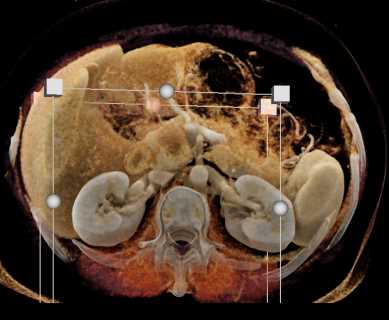

Neuroendocrine Tumor Body of Pancreas